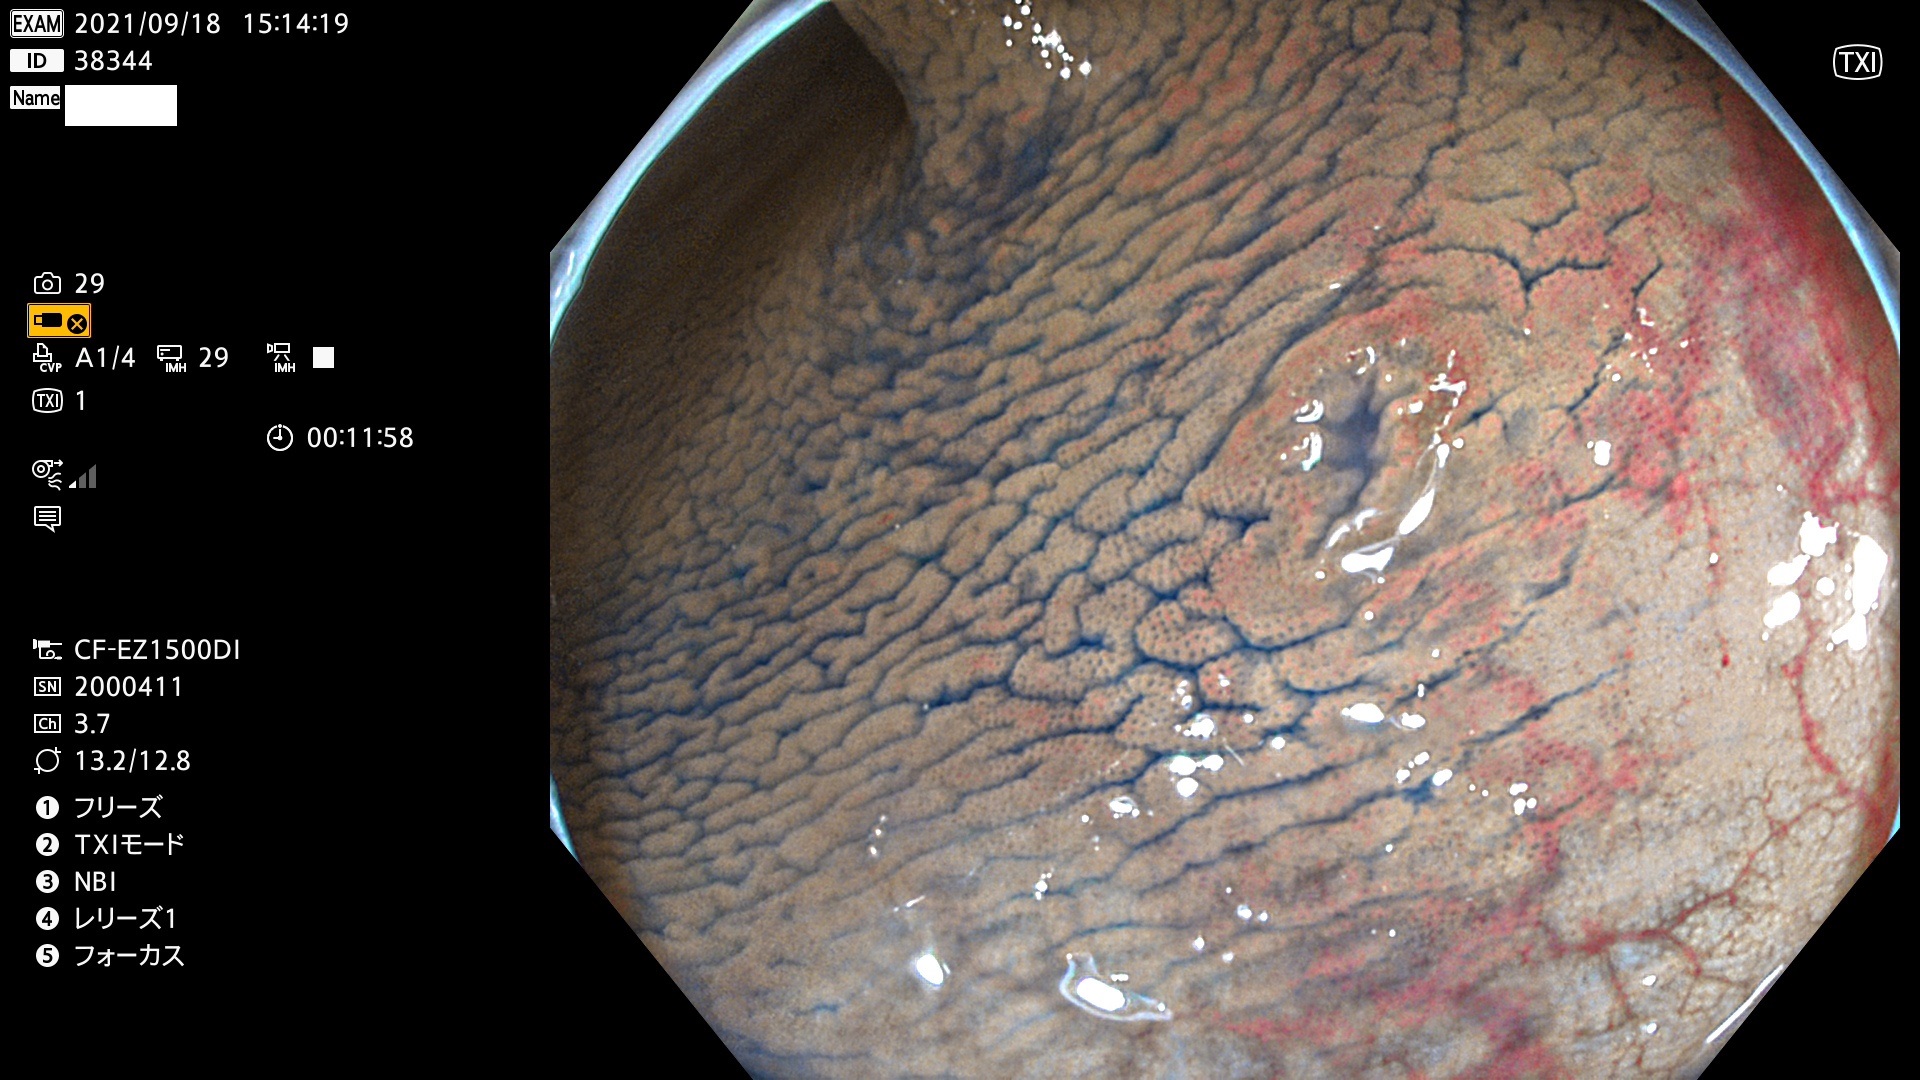

発見困難で危険性の高い平坦型病変(上記100名より抽出)